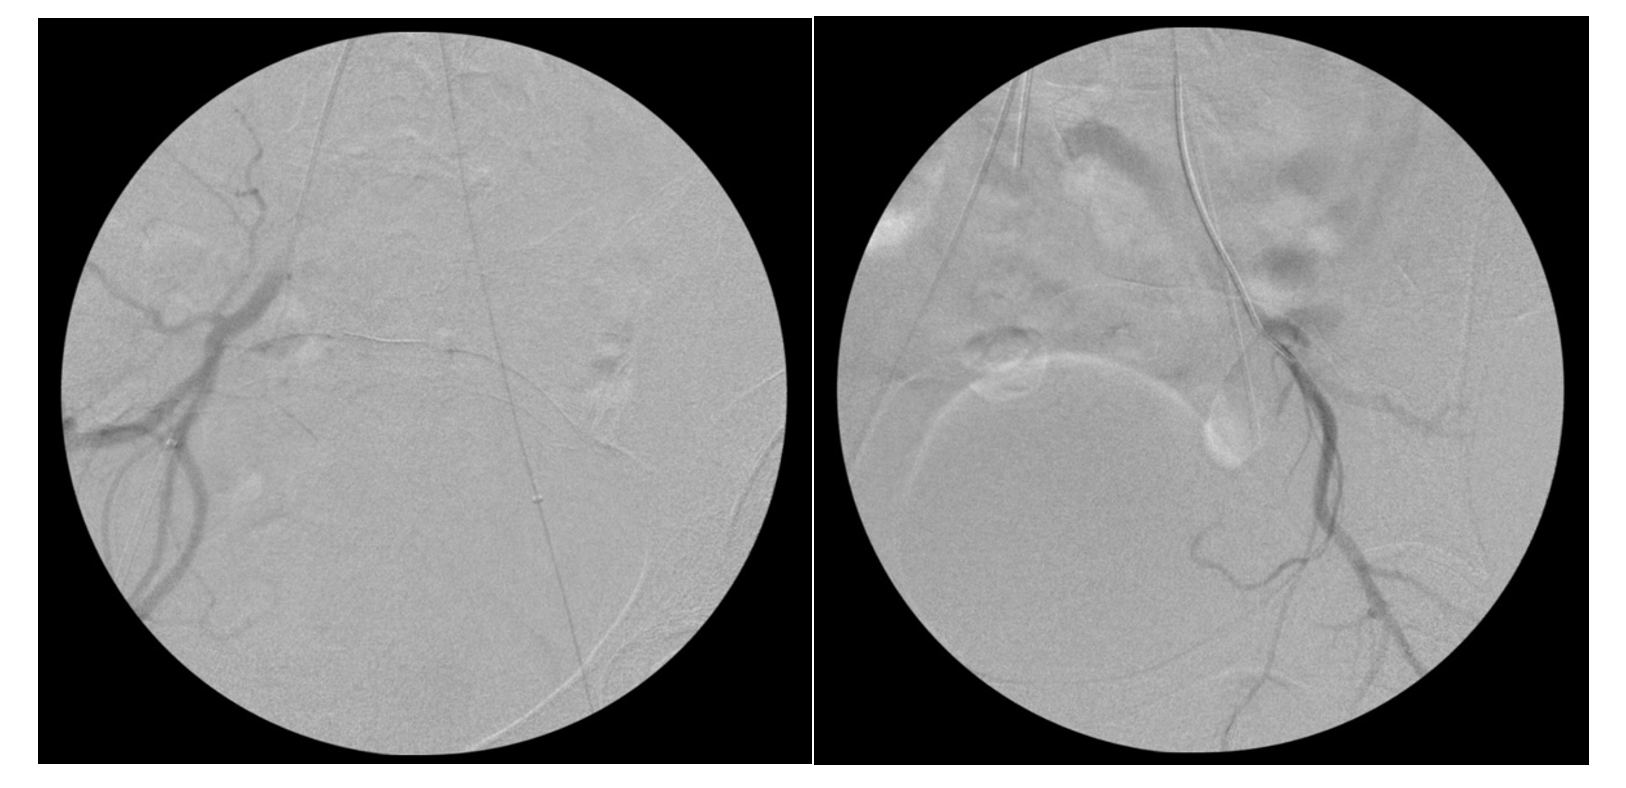

A 29-year-old woman (gravida 3, para 0020) presented to her outpatient obstetrician/gynecologist with heavy vaginal bleeding following a positive home urine pregnancy test. Beta human chorionic gonadotropin (β-hGC) measured 1269.7 mIU/mL. An ultrasound was performed and demonstrated CP measuring approximately 6 weeks’ gestational age with cardiac activity present (Figure 1). Her prior pregnancies included a biochemical pregnancy followed by complete molar gestation, treated with dilation and curettage (D&C). She was subsequently sent to the hospital for intervention. The patient was offered both D&C with vascular IR (VIR) support as well as systemic methotrexate with intra-sac potassium chloride injection, from which she chose the former option.